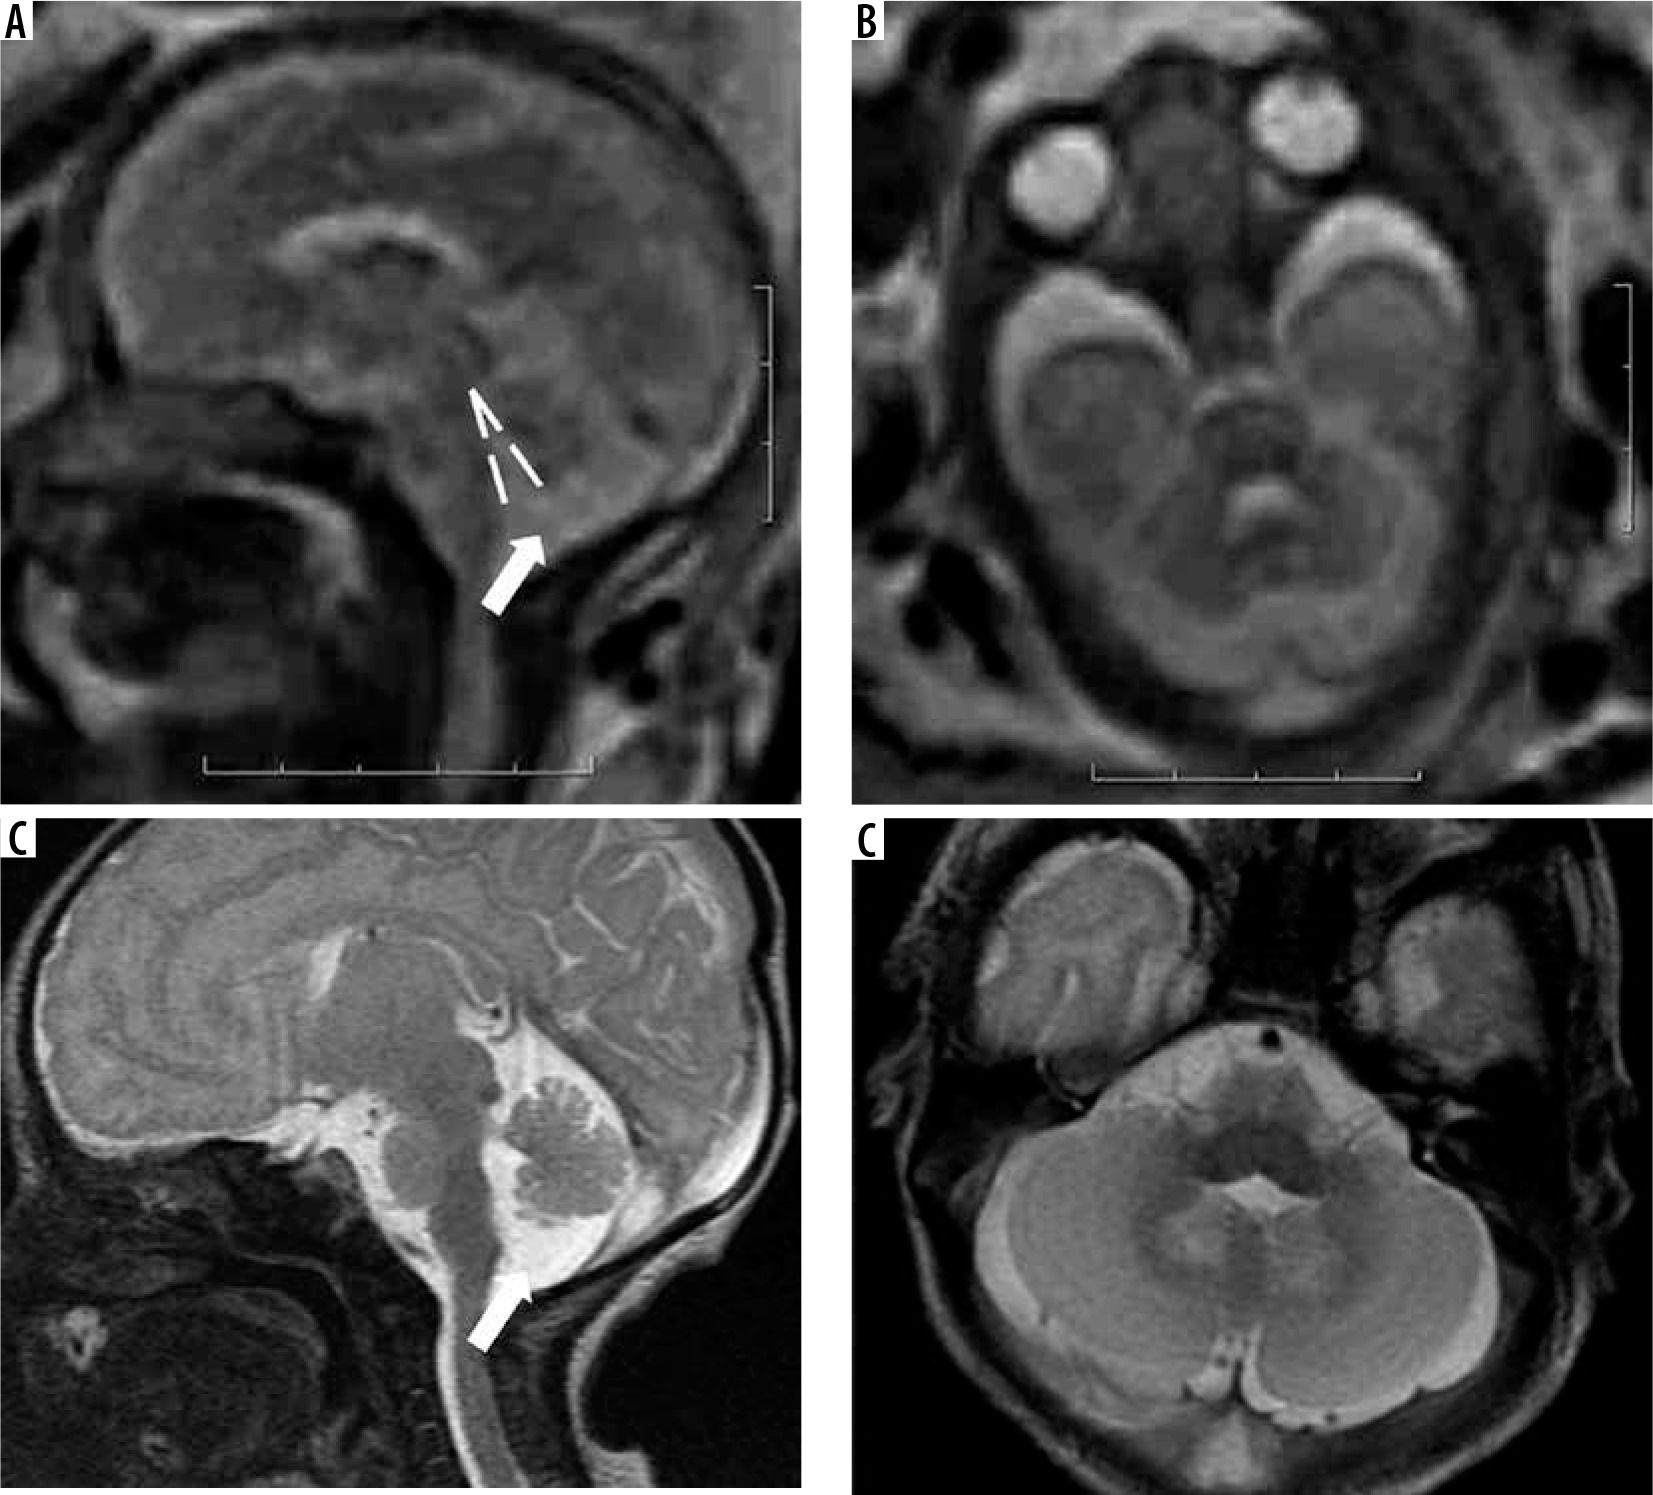

Brainstem predominant malformations

This group consists of malformations such as pontine tegmental cap dysplasia (PTCD), horizontal gaze palsy with progressive scoliosis (HGPPS), and mesencephalic-diencephalic junction dysplasia. PTCD is characterised by flattened ventral pons and a characteristic cap-like protuberance on the dorsal surface of the pons (Figure 14). HGPPS is characterised by butterfly shaped medulla and dorsal pontine cleft. However, these imaging features may be difficult to identify in FMRI.

Figure 14

Pontine tegmental cap dysplasia – gestation age 22 weeks. Axial (A) and sagittal (B) T2w HASTE images show flattened ventral surface of the pons and a small bulge on the dorsal surface of the pons. These findings are more readily apparent in the post-natal MRI images (C and D). Note the cap-like bulge on the dorsal surface of the pons in image D (dotted arrow)